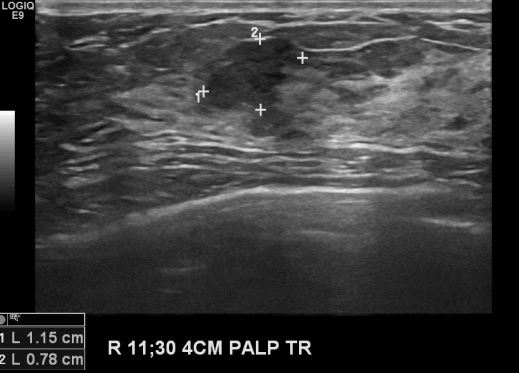

상기환자 우측 유방 만져지는 멍울과 통증으로 내원하신 30대 여성분으로 본원 초음파상

우측 11시 30분 방향에서 4cm 떨어진 거리에 만져지는 멍울 조직검사 시행하여 우측

유관암 진단되었습니다.